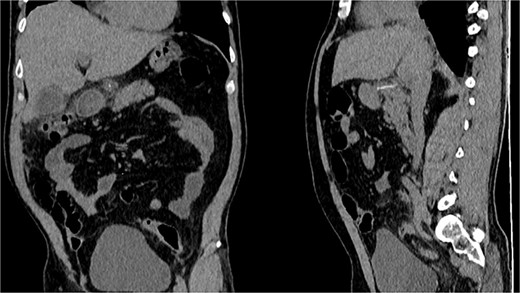

It unveiled a linear hyperdensity behind a thickened stomach wall in the lesser sac, in close contact with the pancreas and duodenum; it had areas of surrounding fat stranding and tissue thickening without pneumoperitoneum. A perforation caused by a fishbone was suspected (Figs 1 and 2).

(A) CT, the fishbone is seen in the lesser sac. (B) Contrast enhanced CT, the fishbone is seen free in the lesser sac in close contact to the pancreas.